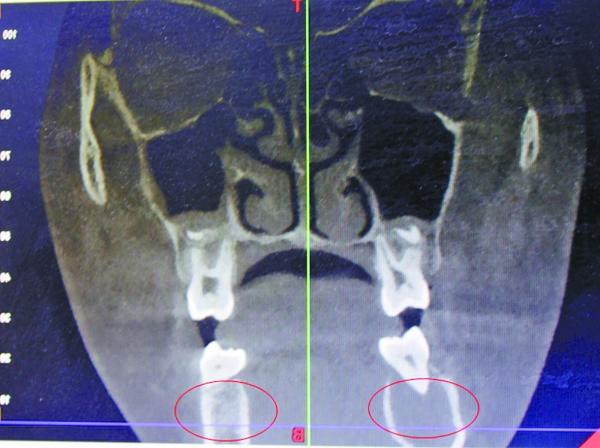

受血管瘤影响,右颌骨发生病变

据口腔医院医生王琨介绍,4月7日,在采取措施止血后,院方迅速为小玉进行了一系列检查,发现其患的是一种非常罕见的颌骨中央性血管瘤?!跋卵啦劾锏亩鲅芊⑸”?,长了若干细微的支血管,将她的颌骨破坏后发生出血?!?/p>

宋庆高博士说,受血管瘤病变影响,女孩的右颌骨,已经形成8×2.5厘米大小的腔窦,“相当于一个空洞。”从方便手术考虑,完全可能将她右侧颌骨去掉,但那样会形成面部缺陷,影响美观,而且右侧无法长牙。